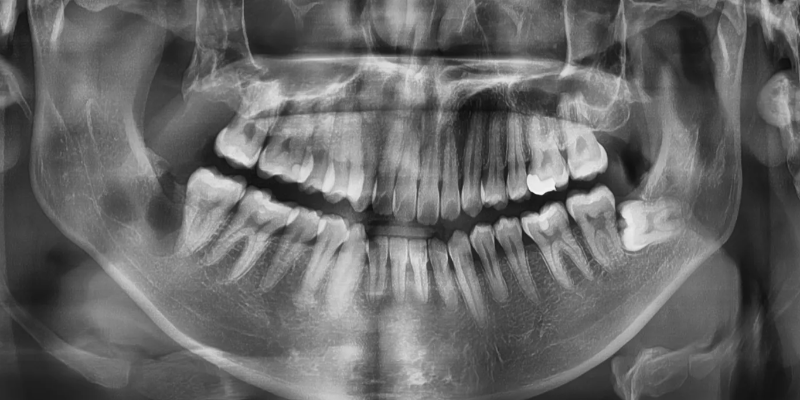

수술은 약 30분 이내에 끝났으며

매복사랑니 발치와 동시에 물혹까지

안전하게 제거할 수 있었습니다.

발치 후 사진

좌측: 치아를 버로 분할하여 제거함

우측: 치관에 잇던 치근낭종을

한덩어리로 깔끔하게 제거함